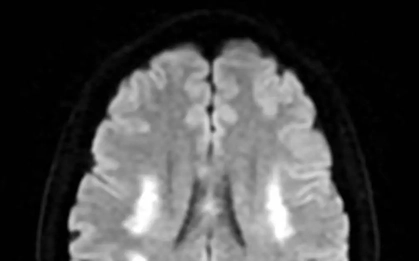

Những năm gần đây, số ca tử vong do đột quỵ não (hay còn gọi là nhồi máu não) đang không ngừng tăng lên, trở thành “kẻ giết người thầm lặng” hàng đầu đe dọa sức khỏe người Việt.